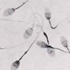

Soy reduces sperm count

With the increased interest in vegetarian and vegan diets a number of young men are turning to alternative foods such as soy, but if you are planning a family it might not be such a good idea. According to a new report in the Journal of Human Reproduction, consumption of even small amounts of soy products can lower a man’s sperm concentration.

Harvard School of Public Health conducted a study and found that the men who ate the most soy had sperm counts far lower than those who reported eating no soy at all. On average, the soy eaters had 41 million fewer sperm per milliliter. The study found that the soy eaters consumed a relatively low amount of 15 soy-based foods including tofu, soy burgers, soy ice cream, soy energy bars, and miso soup — with an average of just one serving of every other day. Now, this may not be significant enough to cause fertility problems, but if you are planning a family then it seems sensible to take every precaution. The study’s lead researcher Jorge Chavarro feels that the evidence is not strong enough one way or the other to deter men from eating soy, but it is known that the isoflavones in soy have long been tied to infertility in animal studies and it seems reasonable to infer they could also affect humans.